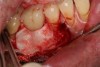

Fig 15. Pretreatment view of a male patient who presented with peri-implantitis after being told by three specialists that the implant would need to be removed.

Figure 15

Fig 16. A circumferential defect of 10 mm to 11 mm was confirmed, and the patient was advised that a technique would be used to treat him but that multiple surgeries and procedures may be required.

Figure 16

Fig 17. The implant had a 12-mm mesial pocket depth, a 12-mm distal pocket depth, bleeding on probing, and perioral exudate.

Figure 17

Fig 18. The patient accepted treatment, and a flap was made. Surface decontamination was achieved without endangering the inferior alveolar nerve.

Figure 18